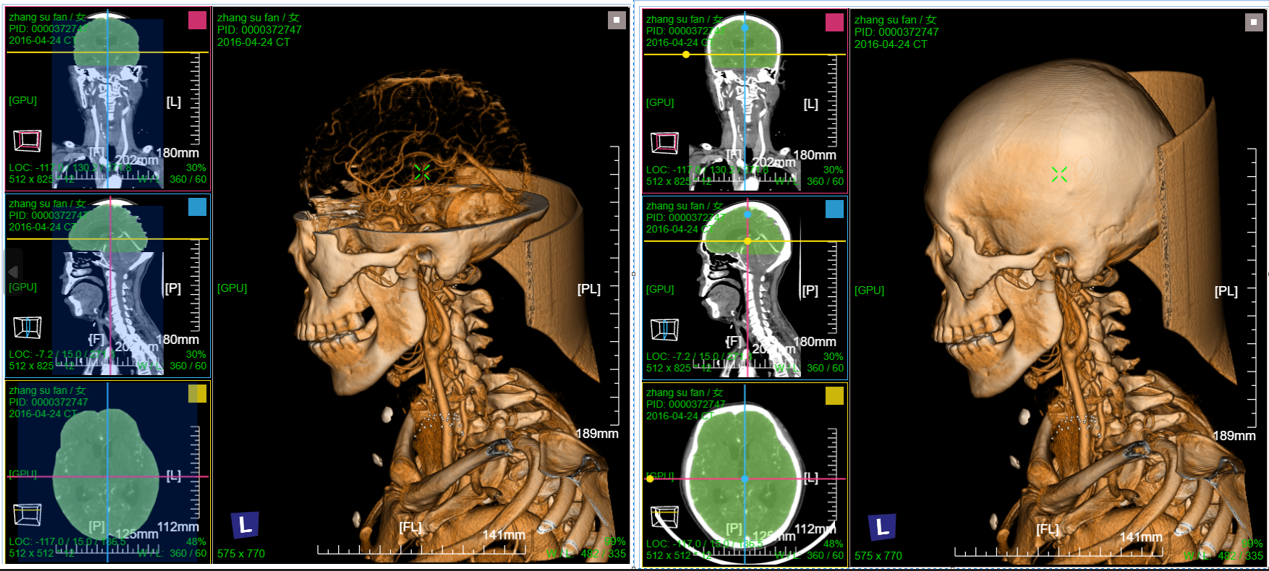

三维:MPR多平面重建(支持任意旋转)、CPR任意曲线切面重建、MIP最大密度、VR容积重建、VE虚拟内窥;任意三维裁剪、一键去床、一键去头骨、快速旋转、厚切MPR(最大密度/最小密度/均值/VR); 手工/半自动分割,分割目标三维渲染; 肋骨CPR拉伸渲染、牙神经管渲染、血管CPR拉直渲染等

八、三维浏览功能操作和截图

左键双击MPR窗口可在MPR三窗口和1x1窗口间切换;三维渲染窗口左键双击在在1x1视图模式和当前视图模式切换

VR渲染一键去头骨:首先进行体包围盒裁剪选择头颅部分限制区域生长范围,然后点击一键去头骨功能

去除头骨后,取消体包围盒裁剪即可;其它操作同vr渲染操作,譬如右键微调VR传输函数,左键三维旋转等

一键去头骨